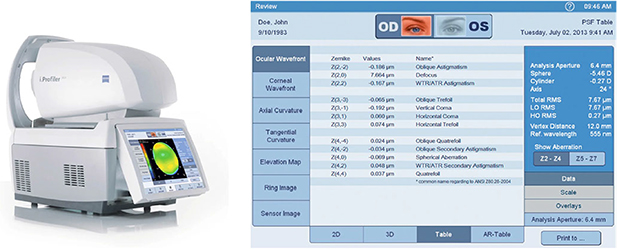

The Zernike polynomials are a complete set of continuous functions orthogonal over a unit circle. Since first developed by Zernike in 1934, they have been in widespread use in many fields ranging from optics, vision sciences, to image processing. However, due to the lack of a unified definition, many confusing indices have been used in the past decades and mathematical properties are scattered in the literature. This review provides a comprehensive account of Zernike circle polynomials and their noncircular derivatives, including history, definitions, mathematical properties, roles in wavefront fitting, relationships with optical aberrations, and connections with other polynomials. We also survey state-of-the-art applications of Zernike polynomials in a range of fields, including the diffraction theory of aberrations, optical design, optical testing, ophthalmic optics, adaptive optics, and image analysis. Owing to their elegant and rigorous mathematical properties, the range of scientific and industrial applications of Zernike polynomials is likely to expand. This review is expected to clear up the confusion of different indices, provide a self-contained reference guide for beginners as well as specialists, and facilitate further developments and applications of the Zernike polynomials.

Standard image High-resolution imageZernike polynomials gradually aroused people's interests after introduction (figure 2) and have found widespread applications in optics and image processing. In 1942, Bernard Nijboer, a PhD student of Zernike, expanded aberration functions of a symmetrical optical system into a series of Zernike polynomials and formulated an efficient representation of the complex amplitude distribution of a point object in the image plane [6]. This work allows analytical evaluation of diffraction integrals and the point spread function (PSF) of a general optical system and is referred to as the Nijboer–Zernike theory. However, the Nijboer–Zernike theory is only valid in the case of small aberrations and can only produce accurate results at positions close to geometrical focus. Seventy years later, Janssen formulated a general expression in terms of power-Bessel series and extended the Nijboer–Zernike theory for optical systems with large aberrations [8]. The extended Nijboer–Zernike theory can analytically compute the PSF of an aberrated optical system described by Zernike coefficients and accelerates further developments in the focused field diffraction theory. While the developments of diffraction theory of aberrations solely rely on analytical derivations, Zernike polynomial-based wavefront analysis depends on the use of computers. In the 1970s, with the rise of adaptive optics, Noll proposed a modified set of Zernike polynomials by normalizing and sorting the polynomials for statistical analysis of wavefront aberrations caused by atmospheric turbulence [9]. At the same time, Loomis at the University of Arizona introduced a reordered subset of Zernike polynomials to the interferogram processing software FRINGE for wavefront analysis in interferometric measurements [10, 11]. This subset called Zernike fringe set contains only 37 terms but has good corresponding relationships with classical aberrations. In 1980, Teague extended the applications of Zernike polynomials from optics to image processing and pioneered Zernike moments, which hold the property of rotation invariance and can be used as shape descriptors for pattern recognition [12]. The Zernike moments have since then become a valuable shape descriptor for image analysis. After entering the 21st century, the developments of Zernike polynomials gradually become mature and several Zernike sets were standardized to promote effective communication by the American National Standards Institute (ANSI) [13, 14] and the International Organization for Standardization (ISO) [15–17] (see figure 3).

Standard image High-resolution imageThe widespread use of Zernike polynomials stems from their unique mathematical properties. First, Zernike polynomials are orthogonal over a unit circle. The orthogonality makes the expansion coefficients of a wavefront function independent of the number of terms [18]. This also enables convenient mathematical manipulations of wavefronts, such as addition, subtraction, translation, rotation, and scaling. Second, while other polynomials orthogonal over a unit disk also exist, Zernike polynomials are unique in the sense that they have good corresponding relationships with classical aberrations, such as astigmatism, coma, and spherical aberration [19, 20]. This enables fast classifications and quantifications of wavefront aberrations. Third, Zernike polynomials make the evaluation of the image quality of an optical system easy since the system PSF can be analytically computed from the Zernike expansion coefficients of wavefront aberrations based on the (extended) Nijboer–Zernike theory [6, 8, 21]. In addition, Zernike polynomials can serve as a basis set for wavefront reconstruction in slope sensitive wavefront sensors, such as the Shack–Hartmann wavefront slope sensor [22, 23] and the lateral shearing interferometers [24], which are important wavefront sensing tools in ophthalmic optics and adaptive optics.